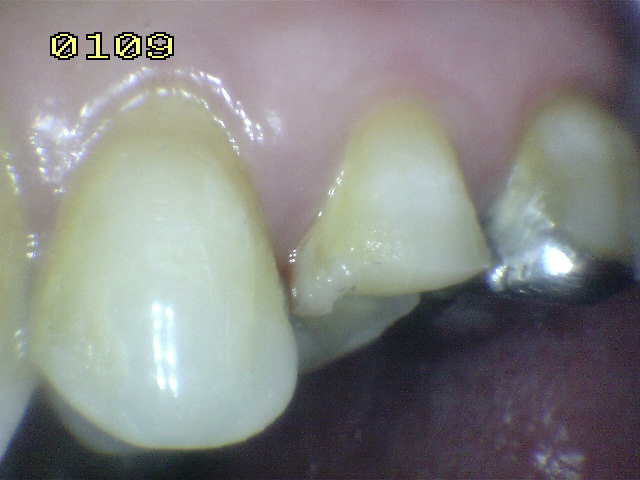

| Pieza

dental 25 para realizar tratamiento de conducto por

necrosis |

Hecho el

tratamiento de conducto, se elimina la totalidad de la

amalgama |

Se bajan en altura las

cúspide palatina, para evitar una futura fractura en

tallo verde. |